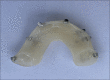

Surgical management of maxillary trauma in pediatric special needs patient using modified cap splint

Pediatric maxillofacial trauma is a rare entity, which is primarily the reason for an individual surgeon's inexperience in managing such injuries. More so, maxillary injuries are infrequent. Pediatric maxillofacial injuries are usually a result of blunt force trauma such as falls, motor vehicle accidents, bicycle injuries, sports-related injuries, assault, and child abuse. The atypical pattern of facial injuries in the pediatric population necessitates each surgeon to approach individual cases with a unique and innovative technique of management, while still following the basic principles of surgical management of maxillofacial injuries. Since facial trauma and surgical interventions both have the potential to lead to disturbance in growth and development, management should be as conservative as possible. The foundation of any surgical intervention must be developed keeping in perspective, the future growth, and development of dentofacial structures. Pediatric facial trauma management is in itself a disconcerting situation for a maxillofacial surgeon, but when a special needs child is involved it becomes an even more perplex decision. We present a case of maxillary trauma in a pediatric patient with global developmental delay, the treatment dilemma, and a review of current literature.